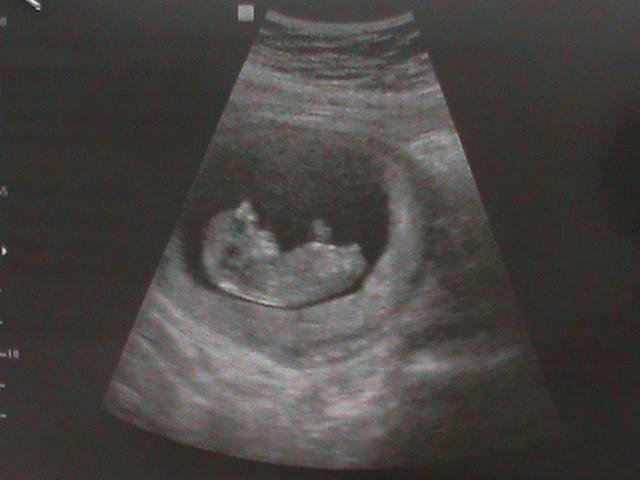

Беременность- 1 триместр ( только до 10 недель)Ну если честно ожидала что то больше. Скрининг делали в той же клинике где и было моё ИИ . Крутой центр, хорошая аппаратура. Пришла а перед домной ещё 2 беременяшки. И как то быстро всё. Ну думаю хорошо, хоть долго не сидеть. Зашла. Легла. Она мне вот ручки вот ножки, вот сердце, вот мозг., вод желудочек. Померила носовую перегородку + шейный отдел. Ну всё говорит. А я спрашиваю. А пол ребёнка?. А она, ну так рано же. Дола мне УЗИ. Я вышла из кабинета. А там. Везде одни+. Ножки, ручки, даже сердце уд.мин. тоже только +. Как то разочаровалось что ли. Сказала узистка что всё хорошо. Соответствует сроку. Я ещё узи делала 2 недели назад. Просто мазня нехорошая была. Но уже в другом центри. Сравнила. Так раньше ставили. Гипертонус матки. А сегодня я ещё спросила про тонус. Она сказала что нету не кого го тонуса. И малыш хорошо за 2 недели подрос.В пятницу иду вставать на учёт. Ну и собственно фото.